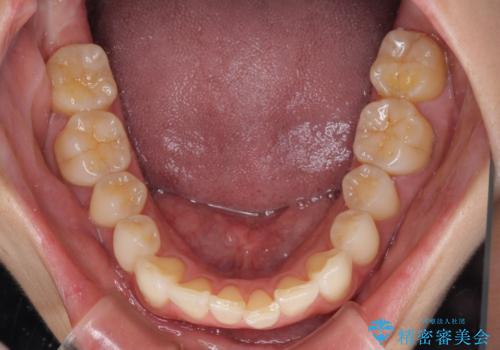

- 奥歯の咬み合わせと、上下前歯の隙間を気にして来院された患者様です。

上顎の歯列全体が、下顎歯列に対して前方に位置しており、その影響で上顎前歯がやや前方に突出している状態でした。